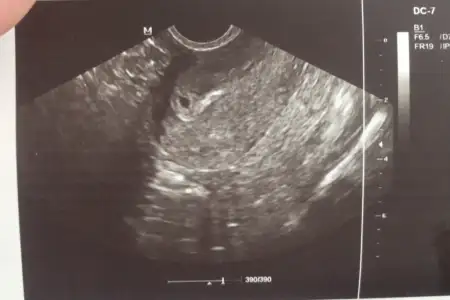

Ben hamile yogasi deneme dersine gidicem yarin. Bakalim.Kızlar aranızda hamile pilatesi düşünen var mı, 13.haftadan sonra gidiliyormuş, doğuma çok faydası var diyorlar, hiç gücüm yok normal doğum olsa zerre ıkınamam sanırım![]()